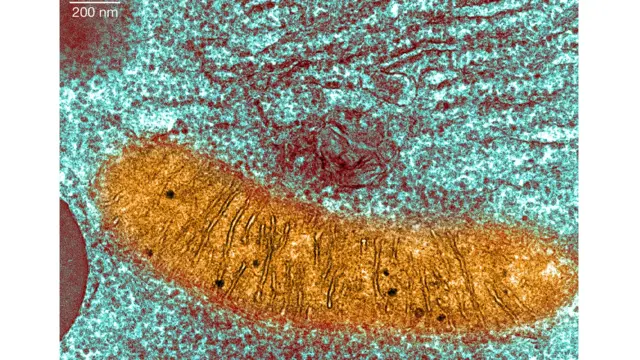

Mitochondria ni sehemu maalum ndani ya seli zetu ambazo hubadilisha nishati inayopatikana kutoka kwenye chakula kuifanya kuweza kutumika kuipa nguvu miili yetu. Lakini haiwezi kufanya hivyo ikiwa inavitu ambavyo vinasababisha magonjwa. Kawaida tunarithi mitochondria kutoka kwa mama zetu, kama mama amebeba mitochondria yenye hitilafu anaweza kuirithisha kwa watoto wake.

Tiba ya upandikizaji wa Mitochondrial ni aina ya IVF inayochanganya DNA kutoka kwa mama na baba ndani ya yai lililotolewa na mwanamke mwingine ambayo ina mitochondria yenye afya, ambayo haina shida wala hitilafu yoyote.

Mimba itakayopatikana itakuwa imebeba Vinasaba ama DNA kutoka kwa wazazi wawili, lakini pia hubeba kiasi kidogo cha vinasaba vya urithi kutoka kwa mtu wa watu aliyechangia yai - karibu 0.1%.